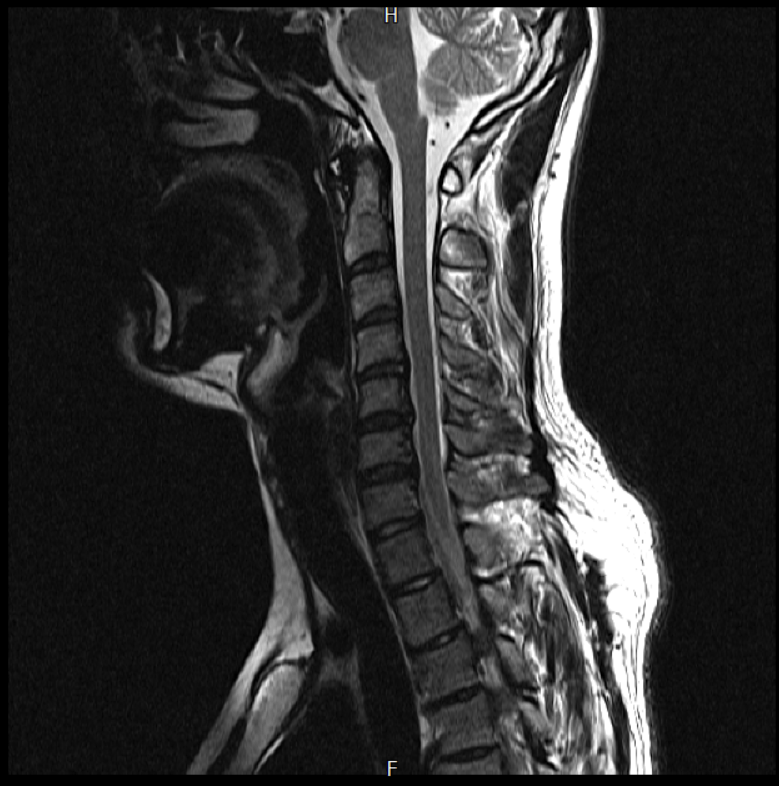

경추 요추 디스크 MRI판독 부탁드립니다.

- 3개월전 좌측 상지 저림(힘빠짐) 발생. 이틀뒤 에 좌측 하지 저림(힘빠짐) 발생.

(힘이 축처지는 느낌이라서 힘빠짐이라고 하지만, 실제 근력 문제, 감각이상, 활동 문제 없음)

-11월, 증상발생 직후 잠실소재 척추전문병원 MRI 요추경추 촬영 후 신경외과 박사 진료, 허리는 매우 건강, 경추는 퇴행성 진행되고 있지만 디스크라고 보기 어려움. 신경막만 살짝 건드리는 정도고 이 정도로 힘빠짐이나 저림이 오지 않고 원인은 다른 곳에 있을 가능성.

1. MRI 상 , 경추와 요추에 디스크가 있나요? 있다면 좌측 팔과 다리에 저림 및 힘빠짐을 줄 정도인가요?

• 2번 째 사진

• 1. MRI 사진을 보았을 때 디스크를 의심해볼 수 있는 소견이 살짝살짝 보이긴 합니다만, 상하지의 저림 및 힘빠짐을 유발할 정도인지는 솔직히 회의적입니다.

2. 영상의 퀄리티는 나쁘지 않아 보입니다. 굳이 재촬영을 하실 필요는 없어 보입니다.

3. 개인적으로는 디스크로 인한 증상이 아닐 것으로 보나, 만약 디스크가 맞다면 우연하게 목과 허리 디스크 발병이 이틀 간격을 두고 나타났을 가능성을 생각해야 하는데, 현실적으로 그 가능성이 높지 않습니다.

4. 말씀하신 것처럼 특히 요추부 MRI는 디스크를 찾기 어렵습니다.

상기 MRI 소견으로는 심한 증상을 보일 정도는 아니며 디스크의 가능성은 적어보입니다.